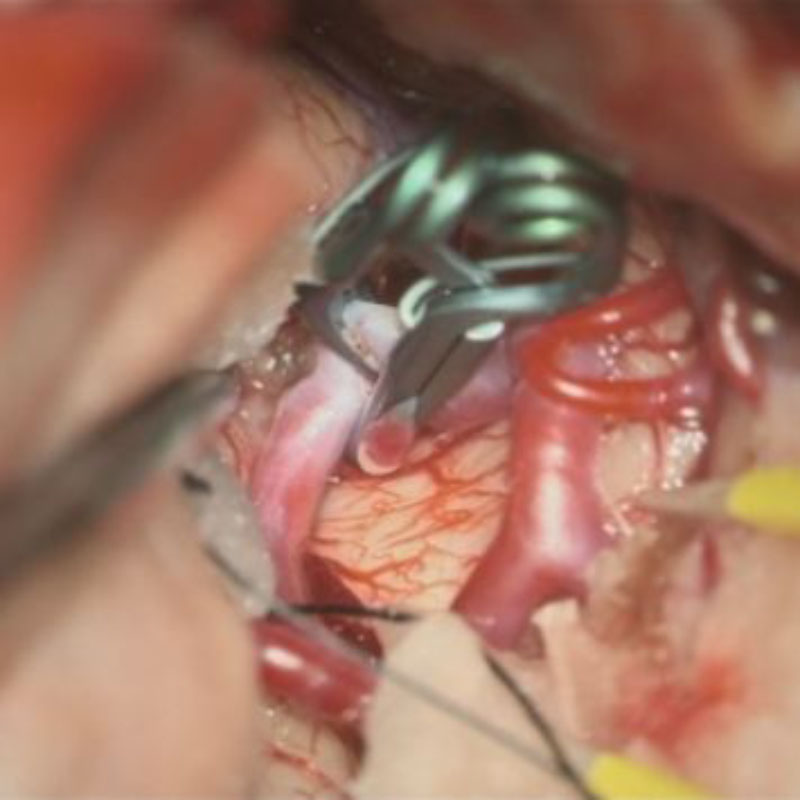

23

'26年5月

60代

前交通動脈瘤

クリッピング術

手術前

クリップ前

クリップ後